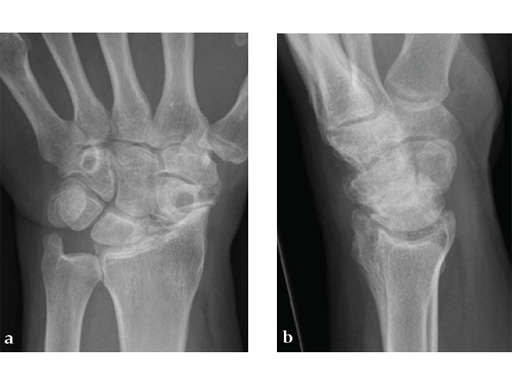

Case 3: Painful SNAC wrist in a 42-year-old man.

Case provided by Juan Gonzlez del Pino, Madrid, Spain

Fig 1 X-ray shows SNAC wrist.